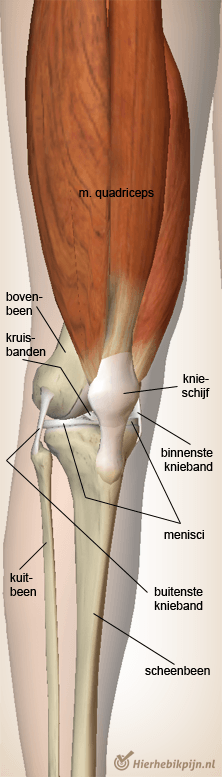

Knie